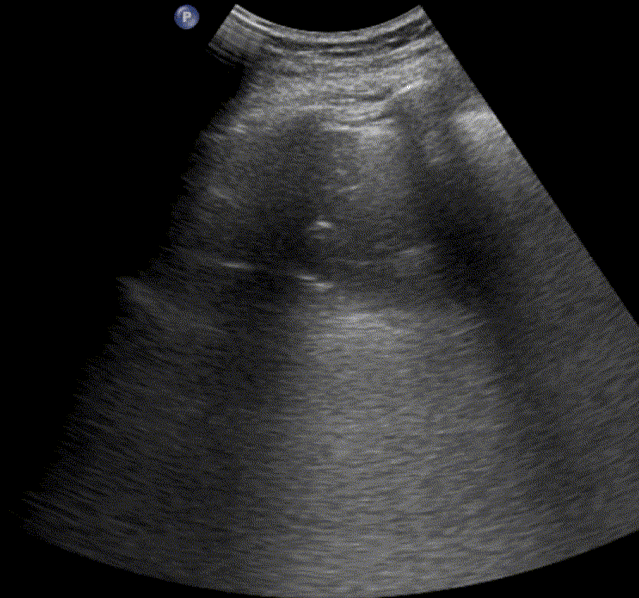

Pleural effusion

Pleural effusion refers to the accumulation of fluid between the parietal and visceral pleural layers. Because pleural fluid gravitates to the most dependent areas, it is typically detected in the lowest portions of the thoracic cavity. Diagnostic sensitivity increases when the patient is in a sitting position, as gravity allows the fluid to collect inferiorly. The lung tissue adjacent to the effusion is often compressed and partially air-depleted.

Scanning the posterolateral chest zones is most effective for identifying pleural effusions. Effusions are commonly found at the lung bases and in the costophrenic angles, where the diaphragm meets the chest wall. Compared with chest radiography, lung ultrasound is both more sensitive and more specific for detecting small volumes of pleural fluid.

Ultrasound can also be used to estimate the volume of pleural effusion. The simplest method is described by Balik et al., which involves measuring the maximal vertical separation (in millimeters) between the diaphragm and the lung base in a supine patient, and multiplying this value by 20 to approximate the pleural fluid volume: Pleural Volume (mL) = Maximal distance (mm) × 20. This formula provides a practical estimation of pleural fluid volume in clinical settings.